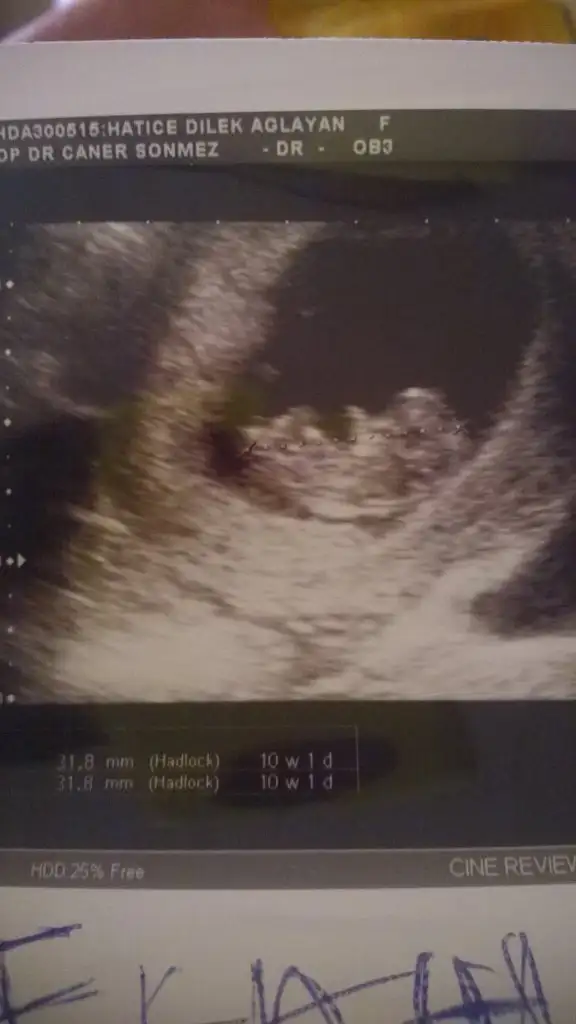

Sanki kiza benzettim benMerhaba, bugün randevumuz vardı ..goruntumuz aşağıda..10+1 haftalığız.. Belli oluyormu sizce, nedir cinsiyetimiz

Canım doktor kesin mi dedi ya bana da 14 + 2 de % 80 - 90 erkek dedi ama emin olamıyorumKızlar benimki erkekmiş![]()

Acaba benim bebiste oylemidir doktor bana göstermedi ki 14 + 2 günlüktü söylediğindeKesin canım

Zaten oluşmuş ciddi ciddi belliydi